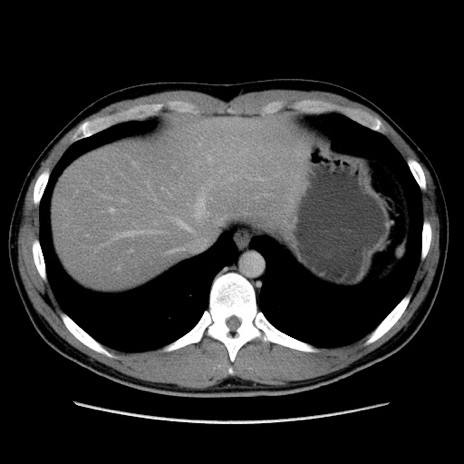

症例36(横断像)

【症例】20歳代 男性

【主訴】心窩部痛

【現病歴】今朝より上腹部痛あり。一旦軽快していたが再度出現したため救急要請。昨日夕に白身の魚を含む刺身を食べた。

【身体所見】BP 136/89mmHg、HR 74/min、BT 37.0℃、腹部:膨満、軟、心窩部に圧痛あり。反跳痛なし、筋性防御なし、腸雑音やや亢進あり。

【データ】WBC 17700、CRP 0.48